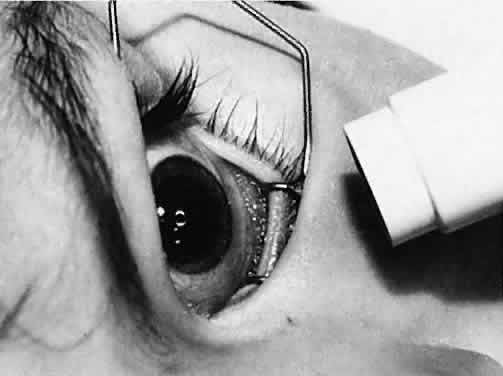

Cataracts that are central in location and larger than 1.5 to 2 mm obstruct light entering the eye sufficiently to reduce visual acuity and impede development of the visual system. In this situation, a trial of dilating the pupil with topical applications of 2.5% phenylephrine drops three times a day to allow light to enter around the opacity may result in an improvement in visual acuity. Pupils that dilate poorly with phenylephrine may respond to 0.5% atropine eyedrops; however, the accompanying cycloplegia necessitates the use of bifocals to correct the cycloplegic refractive error and the lack of accommodation. Frequent monitoring of visual acuity and pupil size at different times of the day and under different lighting conditions is recommended. Improvements in acuity may be temporary if the lens opacity progresses in size.

Usually, anterior polar cataracts are visually insignificant and allow normal visual development (see Fig. 1). However, some affect vision, and all require careful monitoring.7 Centrally located cataracts that are on or near the posterior lens capsule have a greater effect on the refraction of light and visual acuity (Fig. 2). Nuclear cataracts associated with metabolic disorders or prenatal infections produce double refracting systems that cause optical distortion and significantly decrease visual acuity (Fig. 3).

Visual Acuity and Signs of Visual Function

Ultimately, it is the measured or estimated level of visual acuity or acuity potential that determines the need for cataract surgery. If either the measured or the estimated decrease in visual acuity produced by the cataract is sufficient to prevent adequate visual development or if signs of significantly decreased visual acuity, such as strabismus or poor central fixation, are present, cataract surgery is indicated. Use of the Teller visual acuity cards at periodic intervals can help to measure visual acuity.10 In some children, visual acuity that is below normal or decreasing can be documented accurately to support the decision to perform cataract surgery (Figs. 4 and 5). Care must be taken in interpreting Teller visual acuity data because the normal levels in young infants and children are low and span a wide range. The Teller acuity card measurement of grating visual acuity may severely underestimate the level of visual loss in patients with cataracts and amblyopia.11